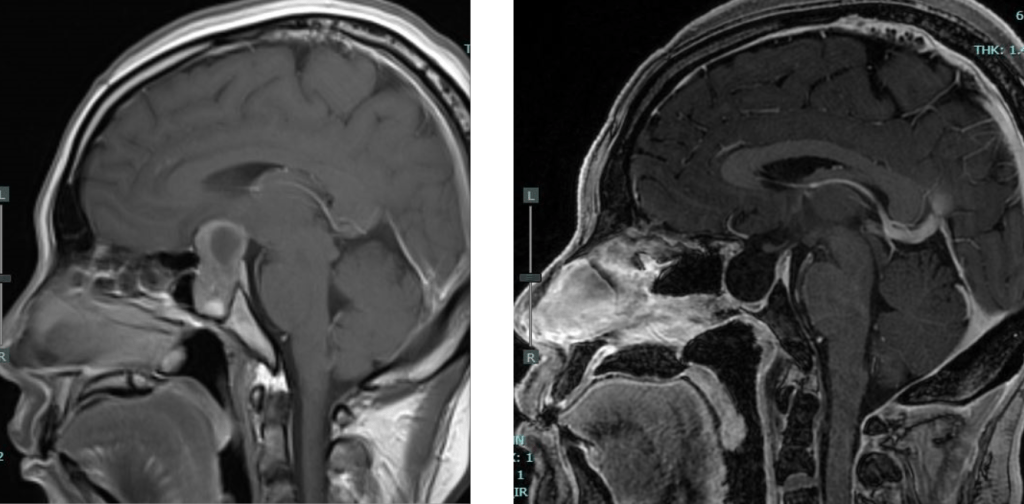

จากประวัติและการตรวจร่างกายหากแพทย์สงสัยว่าผู้ป่วยอาจมีเนื้องอกต่อมใต้สมองแพทย์จะทำการตรวจต่อด้วยการส่งภาพรังสีวินิจฉัยซึ่งมักจะทำเป็นMRIเพื่อให้ได้ข้อมูลเกี่ยวกับตัวเนื้องอกและโครงสร้างทางระบบประสาทมากที่สุด และเมื่อได้การวินิจฉัยว่าเป็นเนื้องอกต่อมใต้สมองแล้ว การรักษาต่อจะมีทีมแพทย์ที่เข้ามาเกี่ยวข้องหลายแผนกทั้งอายุรแพทย์ต่อมไร้ท่อ, ประสาทศัลยแพทย์, จักษุแพทย์, แพทย์รังสีรักษาเป็นต้น เพื่อร่วมประเมินและดูแลรักษาผู้ป่วยต่อไป